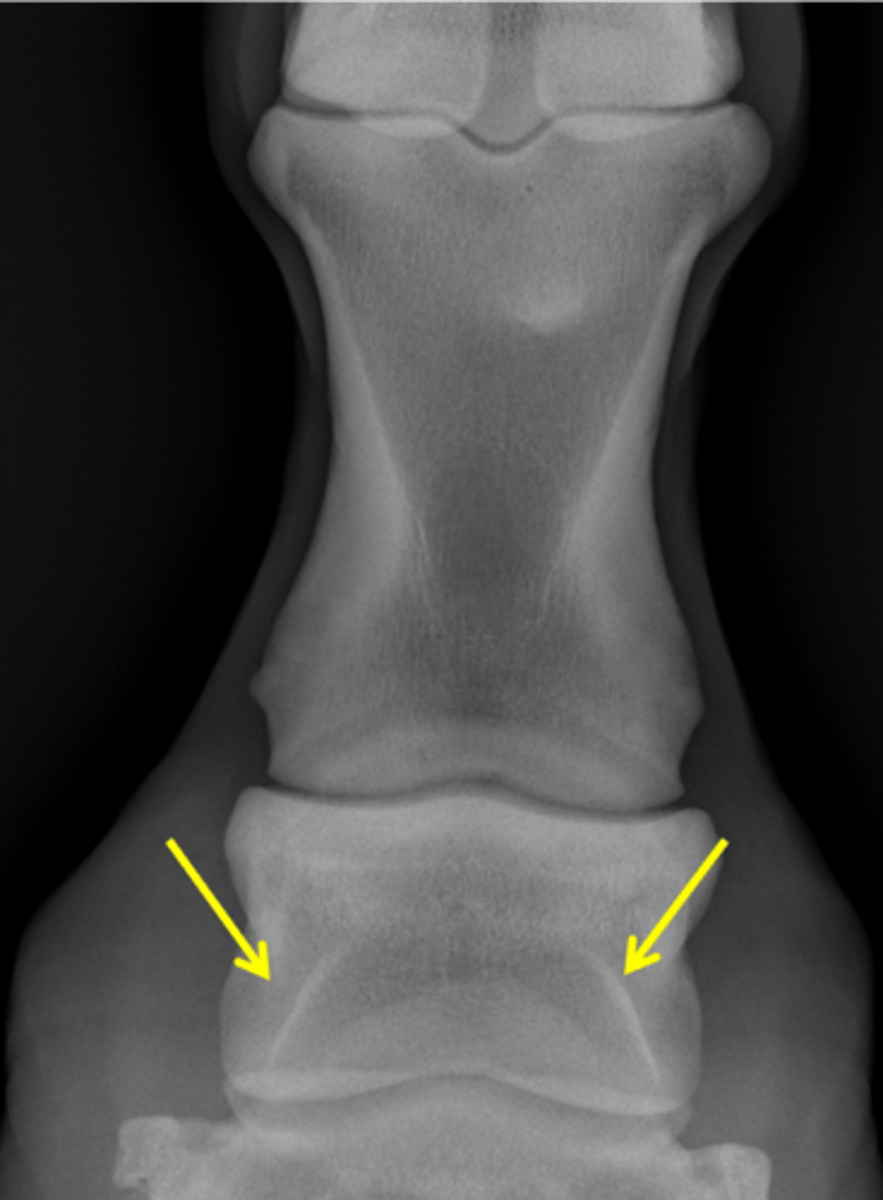

Fetlock joint, DP

ID joint and view

Proximal sesamoid bones

Sagittal ridge

Attachment of collateral ligaments

Proximal sesamoid bones

Palmar process of P1

Condyles of the third metacarpal bone